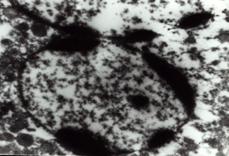

一、細胞凋亡的形態學檢測

根據凋亡細胞固有的形態特徵,人們已經設計了許多不同的細胞凋亡形態學檢測方法。

(1)未染色細胞:凋亡細胞的體積變小、變形,細胞膜完整但出現發泡現象,細胞凋亡晚期可見凋亡小體。

貼壁細胞出現皺縮、變圓、脫落。

(2)染色細胞:常用姬姆薩染色、瑞氏染色等。凋亡細胞的染色質濃縮、邊緣化,核膜裂解、染色質分割

成塊狀和凋亡小體等典型的凋亡形態。

肝細胞凋亡一般以細胞核染色質的形態學改變為指標來評判細胞凋亡的進展情況。

結果評判:細胞凋亡過程中細胞核染色質的形態學改變分為三期:Ⅰ期的細胞核呈波紋狀(rippled)或呈折縫樣(creased),部分染色質出現濃縮狀態;Ⅱa期細胞核的染色質高度凝聚、邊緣化;Ⅱb期的細胞核裂解為碎塊,產生凋亡小體。